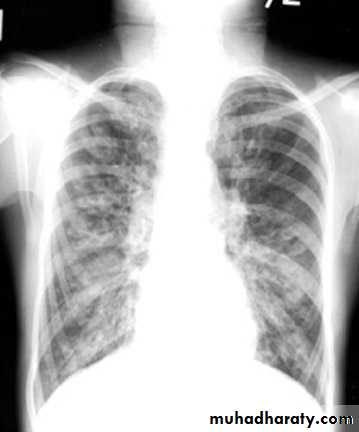

Bronchiectasis

Mucous in the airways cannot be easily cleared fromthe lungs

Nasal PolypsDigital ClubbingSchamroth sign +v